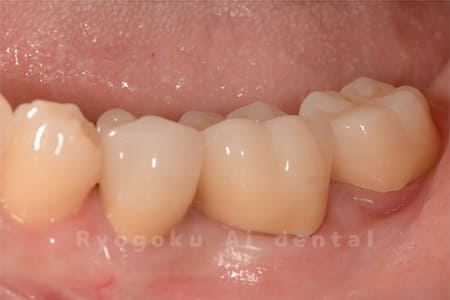

Case11

- 治療内容

- セラミッククラウン、セラミックインレー

-

- 治療費用

- 123,000円×2(セラミッククラン)、77,000円(セラミックインレー)

銀歯が取れて、ご来院された患者様です。奥歯2本をセラミッククラウン、手前の小臼歯をセラミックインレーで治療を行いました。

<リスク・副作用>

過度の咬合や衝撃で割れることがあります。